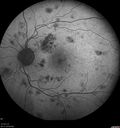

Hairy Cell Leukemia - Retinal Hemorrhage and twig Branch Vein Occlusion764 views79 year old man He has had hairy cell leukemia since 2002. He is in remission. His last blood tests were 9/2018. He just moved down here and needs a new leukemia doctor. His vision is fine.

VA OD: Dcc20/25

VA OS: Dcc20/25

IOP: TP: OD:12 OS:12